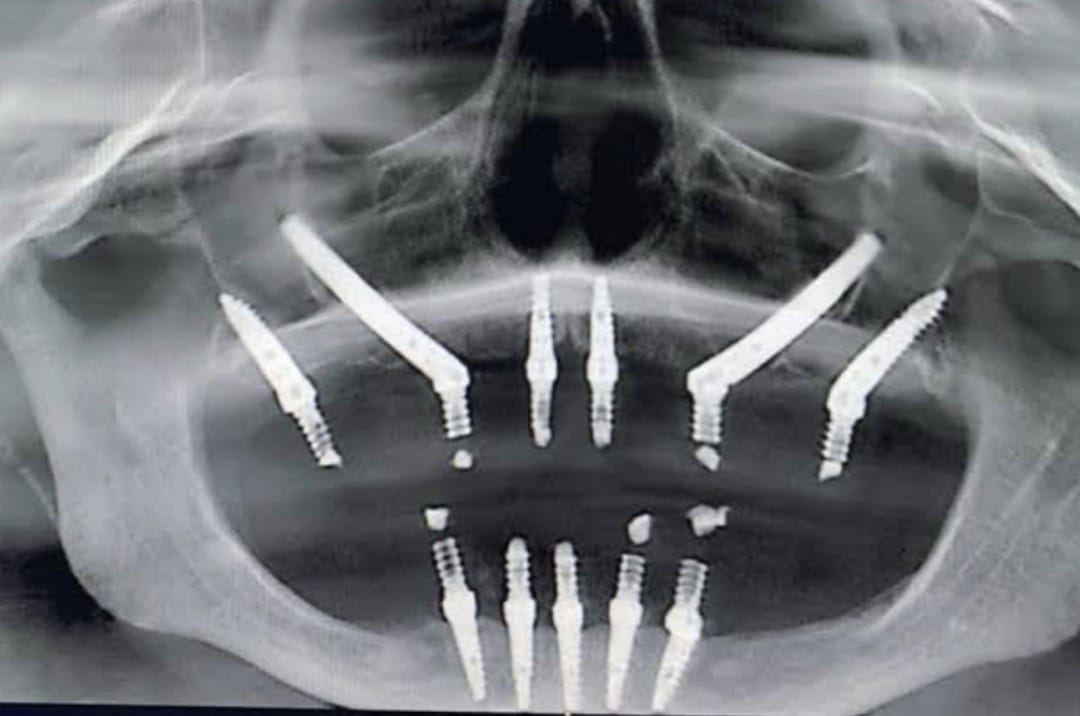

Prosthodontic treatments include a wide range of procedures such as dental crowns, bridges, dentures, and implant-supported restorations. These treatments are designed to replace missing teeth, restore damaged teeth, and improve the alignment and function of the bite. Each treatment plan is customized based on the patient’s oral condition, bone structure, and individual needs. Advanced techniques and modern materials are used to ensure durability, comfort, and natural aesthetics. Dental implants, combined with prosthetic crowns, provide one of the most effective and long-lasting solutions for tooth replacement. Removable and fixed prosthetic options are also available depending on the number of teeth missing and patient preference. Proper planning, regular dental check-ups, and good oral hygiene are essential to maintain the longevity of prosthodontic treatments. With the help of prosthodontics, patients can regain proper chewing ability, clear speech, and a balanced facial appearance, ultimately improving their overall confidence and well-being.